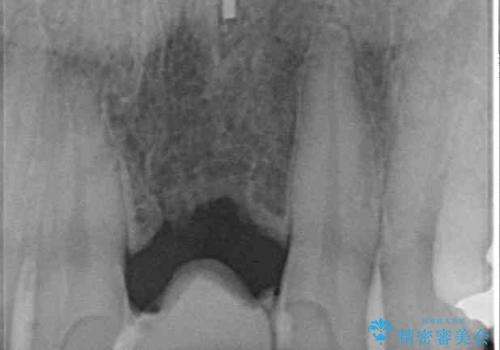

- 接着タイプの前歯のブリッジが不自然であるとのことで来院された患者様です。

欠損部の歯肉が窪んでいるため、歯肉移植により形態を改善し、オールセラミックブリッジにて補綴することとしました。

事前に装着されていた接着タイプのブリッジは、歯の切削量が少ない反面、接着界面から虫歯が進行しやすく、脱落リスクが高くなるというデメリットがあります。